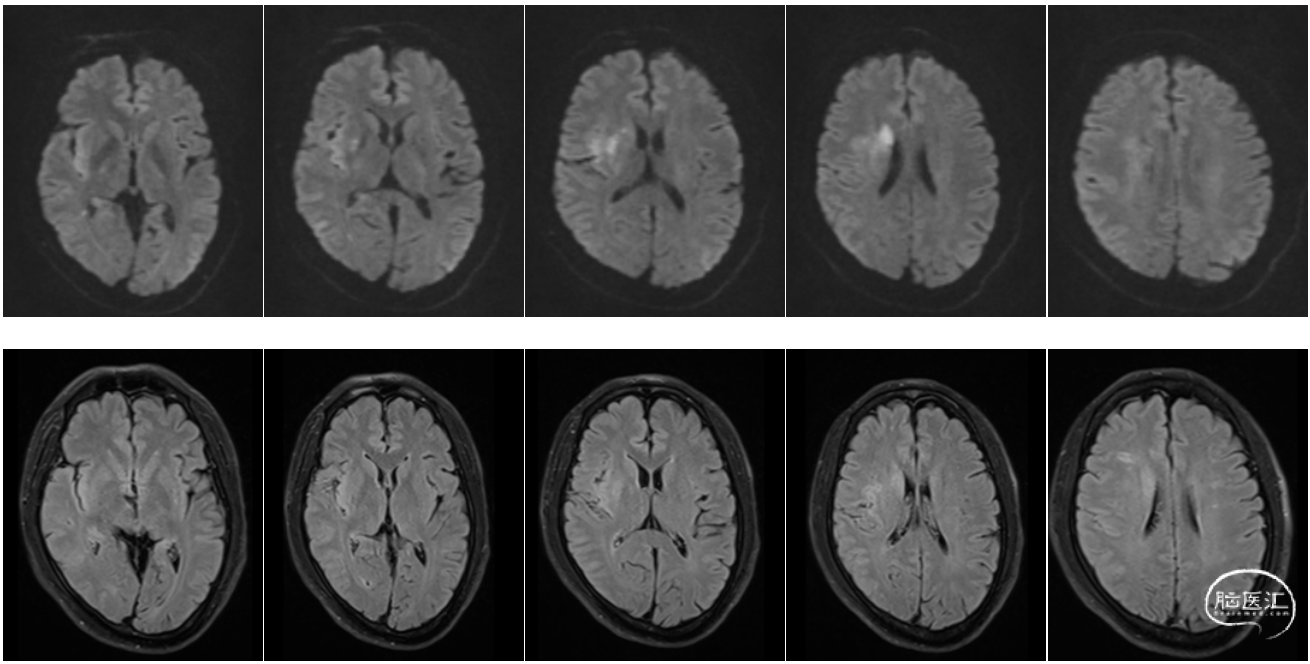

急诊医生接诊后立即启动卒中绿道,同时请神经内科的绿道医生会诊,查头颅CT、心电图、血糖生化等检查,神经内科医生到达后,立即行神经系统查体,此时的患者比来院前症状要减轻一些,仅有轻微的构音不清以及左侧轻微面瘫。NIHSS评分2分(面瘫1分+构音1分),属于轻型非致残性卒中,但随后的颅脑卒中MR检查,结果提示右侧半球急性脑梗死。

MRA示:右侧大脑中动脉闭塞

1周后患者NIHSS评分:2分(面瘫1分+共济失调1分),mRS评分:2分。复查头MR提示右侧大脑中动脉血流通畅,顺利出院。